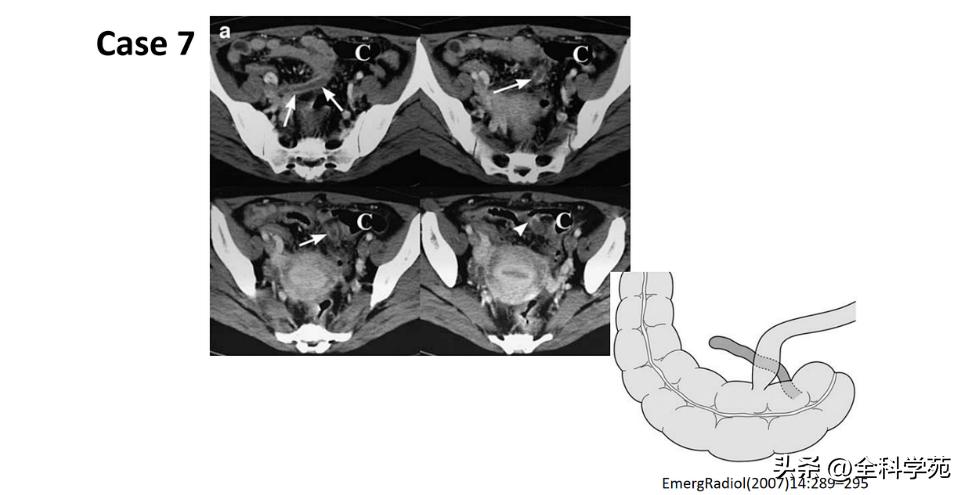

◆ 穿孔 (Perforation)

◆ 局部低强化是穿孔征象

◆ 蜂窝织炎和脓肿 (Phlegmon and abscess

◆ 小肠梗阻 (Small bowel obstruction)